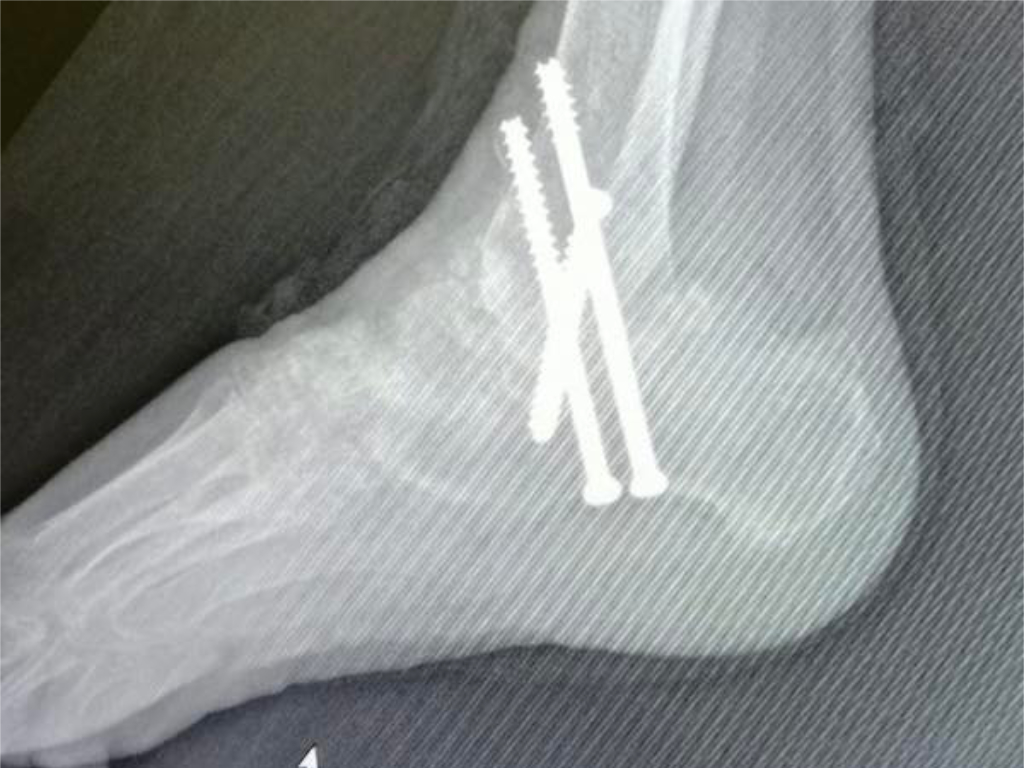

Last year we straightened up the right foot of a patient with severe deformities due to rheumatoid arthritis. Last week we gave her a matching pair. We were all delighted with the results!